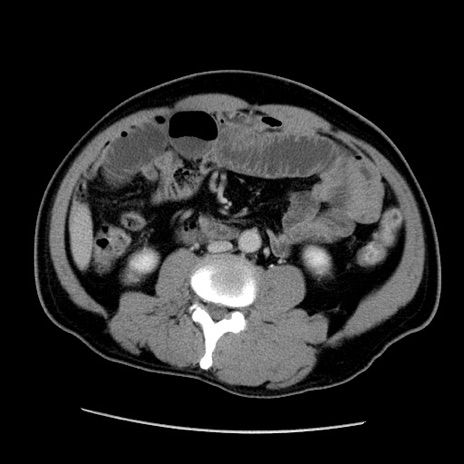

症例22(横断像)

【症例】50歳代男性

【主訴】腹痛

【現病歴】AVMからの被殻出血のため回復期リハ病棟入院中。 本日午後3時頃急に下腹部痛が出現した。

【既往歴】AVM、被殻出血、虫垂炎、高血圧

【身体所見】意識晴明、左半身不全麻痺、会話の理解は良好、36.5°C、腹部:膨隆、全体に板状硬、下腹部正中に圧痛点あり、反跳痛-、筋性防御不明、右下腹部にope scar

【データ】WBC 9400、CRP 0.06